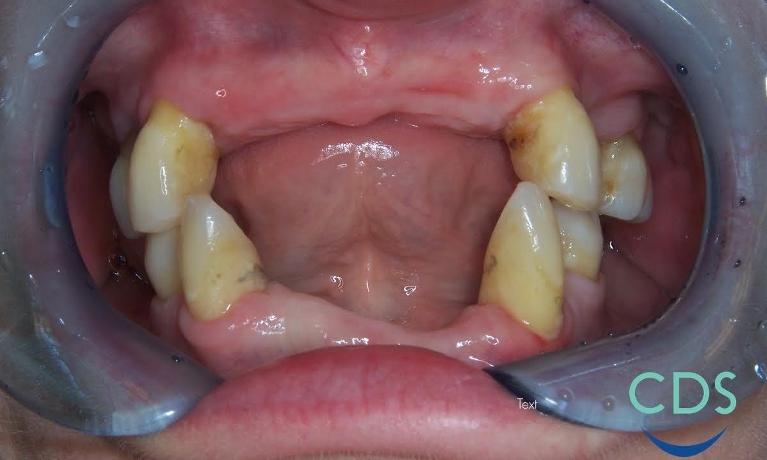

Smile Gallery: Full & Partial Dentures

We've assembled a selection of Before and After photos of some of our actual patients. You can see the outstanding results we've achieved for them, so why not give us a call and let's see what we can do for you!